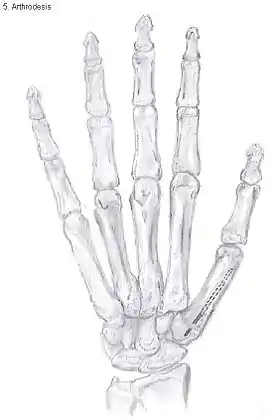

Arthrodesis

Arthrodesis of the CMC1 joint is a surgical procedure in which the trapezium bone and the metacarpal bone of the thumb are secured together. Because the joint is fixed, and therefore can not be moved, the complaints of the patient are mainly gone.During the surgery the two bones will be fixated using K-wires. The use of plates and screws has also been described. The thumb will be positioned in a way it can still perform a pinch grip. Because of the fixation, the two bones will fuse together. This will occur usually within four to six weeks.

However, this technique has some disadvantages.[27] The palm of the hand is unable to be flattened, making it difficult to wear gloves or put your hand in a pocket. Because the stress on the CMC1 joint is now divided over the other joints, those joints are more likely to be damaged.[34]

Nevertheless, this procedure can be used in patients with stage II and III CMC OA as well as in young people with posttraumatic OA.[27]